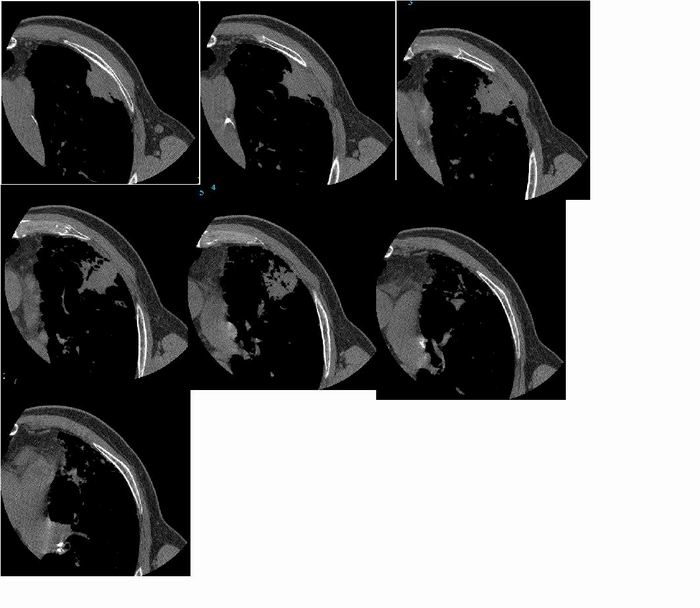

标题: 男,72岁,咳嗽,咯痰,进日痰中带血 [打印本页]

标题: 男,72岁,咳嗽,咯痰,进日痰中带血

不能排除周围型肺癌。

肺癌并淋巴管炎

考虑细支气管肺泡癌可能性大。

周围型肺癌,并阻塞性炎症

图像太局限,只能考虑左肺周围型肺癌。

不排除左肺周围型肺癌。

考虑炎症,不排除左肺周围型肺癌

考虑 左肺周围型肺癌

考虑细支气管肺泡癌

左肺周围型肺癌。

首先考虑炎性改变(结核),不除外周围性肺癌   肺间质增生部分纤维化  支气管扩张并感染

周围型肺癌可能

考虑:左肺周围型肺癌。

考虑左肺周围型肺癌。

考虑肺癌